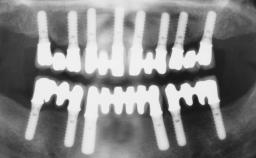

Surgical treatment of a 68-year-old female patient who experienced failure of her conventional bridge in the right maxilla. After removal of the compromised abutment teeth and a healing period of 6 weeks, a sinus floor elevation procedure using the lateral window technique and a composite graft to correct the insufficient bone height is carried out.

Two dental implants are placed in the same surgical session. The case concludes with the presentation of the final fixed dental prosthesis with a distal cantilever unit.

The 1-year follow-up radiographs demonstrate successful sinus floor elevation and stable bone crest levels around both implants, leading to a favorable long-term prognosis of the implant-supported prosthesis.

# of Implants 2

Bone Augmentation Simultaneous|Sinus Floor Elevation

Augmentation Materials Autogenous chips|Xenogenous